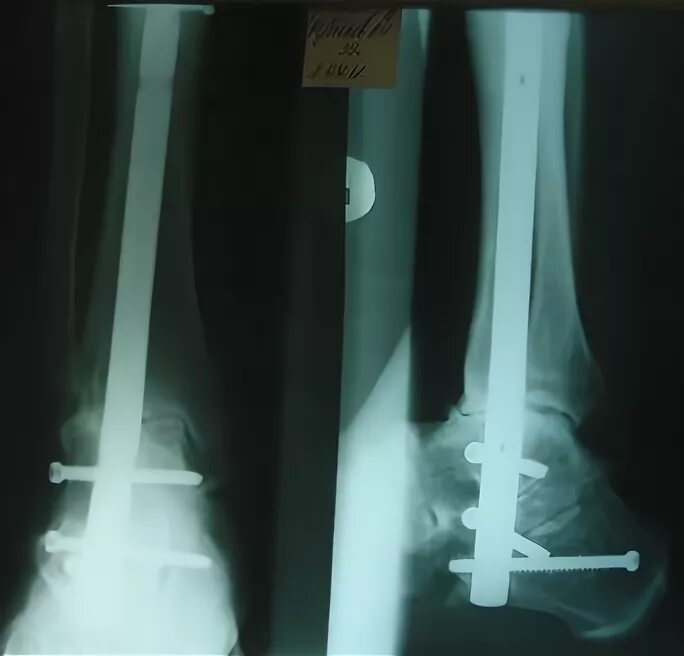

Артродез форум